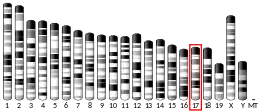

Reductions in expression of DNA repair genes (usually caused by epigenetic alterations) are very common in cancers, and are ordinarily much more frequent than mutational defects in DNA repair genes in cancers. (See Frequencies of epimutations in DNA repair genes.) In a study of MSH2 in non-small cell lung cancer (NSCLC), no mutations were found while 29% of NSCLC had epigenetic reduction of MSH2 expression.[39] In acute lymphoblastoid leukemia (ALL), no MSH2 mutations were found[40] while 43% of ALL patients showed MSH2 promoter methylation and 86% of relapsed ALL patients had MSH2 promoter methylation.[41] There were, however, mutations in four other genes in ALL patients that destabilized the MSH2 protein, and these were defective in 11% of children with ALL and 16% of adults with this cancer.[40]

Methylation of the promoter region of the MSH2 gene is correlated with the lack of expression of the MSH2 protein in esophageal cancer,[42] in non-small-cell lung cancer,[39][43] and in colorectal cancer.[44] These correlations suggest that methylation of the promoter region of the MSH2 gene reduces expression of the MSH2 protein. Such promoter methylation would reduce DNA repair in the four pathways in which MSH2 participates: DNA mismatch repair, transcription-coupled repair[5] homologous recombination,[6][45][46] and base excision repair.[7] Such reductions in repair likely allow excess DNA damage to accumulate and contribute to carcinogenesis.

The frequencies of MSH2 promoter methylation in several different cancers are indicated in the Table.